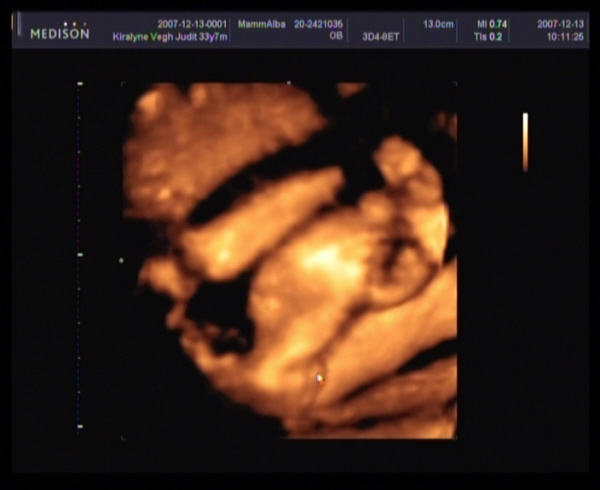

Judy,

gyere a képekkel!!!! Nagyon kíváncsi vagyok Barbikára!!!!!